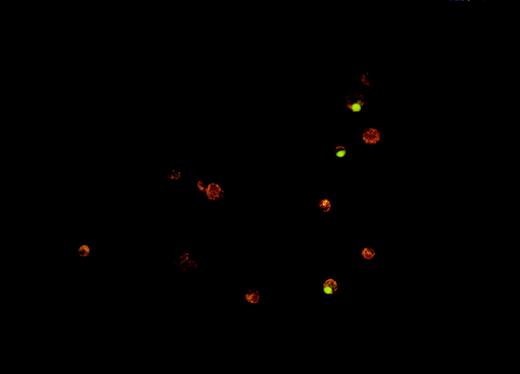

One of the main physiologic advantages of apoptotic death compared with necrotic death derives from how the cells are cleared from tissues. It is believed that apoptotic cells are taken up and removed from tissues by phagocytosis, either by professional phagocytes (eg, tissue macrophages) or by other neighboring cells.18 We sought to determine whether oxidative stress interferes with phagocytosis of dying tumor cells, given that it inhibits the induction of apoptosis. A fluorescence microscopy–based in vitro assay was developed for measuring phagocytosis of apoptotic Burkitt lymphoma cells by human monocyte-derived macrophages. A photograph of a representative result from this assay is shown in Figure 6.

Fluorescence microscopy assay for phagocytosis of Burkitt lymphoma cells by human monocyte-derived macrophages.

The phagocytosis assay was performed as described in Materials and methods. The photograph shows 3 macrophages (red-orange cells), which have engulfed VP-16–treated ST-486 (green) cells.